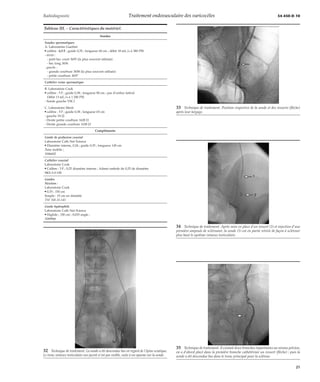

16 Traitement du côté droit (deux cas différents).

A, D. Opacification.

B, E. Mise en place d’un microcathéter (1), dont l’extré-mité

(flèche) est en regard de l’épine sciatique.

C, F. Contrôle en fin de traitement : thrombose du sys-tème

veineux testiculaire au niveau lombaire.

17 Traitement du côté gauche (3 cas différents).

Cathétérisme aisé de la veine testiculaire unique sans problème. En (A, C, E) aspect

avant traitement, en (B, D, F) après traitement, mise en place de ressorts (flèche) et in-jection

de sclérosant.